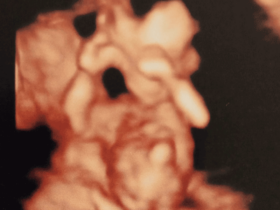

“Vivir siempre como mamá soltera es duro, pero al ver a mis hijos me doy cuenta que ellos son mi hogar y no cambiaría nada con tal de tenerlos a mi lado. A los 17 tuve a mi primera hija y no esperaba volver a ser mamá, pero cuando cumplí 30 sentí que quería gozar esa etapa de nuevo.” “Al no tener pareja, pensé que una manera de poder ayudar y calmar esa sensación era donando mis óvulos. Investigué dónde podía hacerlo y encontré al Instituto, me hicieron exámenes y les conté por qué quería hacerlo. Cuando regresaron con los resultados, un médico habló conmigo y dijo que, a pesar de ser joven, tenía una baja reserva ovárica y no era candidata para donar; pero, si así lo quería, podía acudir a una consulta de valoración para un tratamiento de Reproducción Asistida.” “Lo pensé mucho, pero al final no quise perder la oportunidad. Al finalizar mi diagnóstico, me hicieron una propuesta económica que se elevaba mucho de mis posibilidades, pero no dije que no, y les pedí tiempo para poder reunir el dinero.” “Cuándo logré reunirlo todo estaba muy ansiosa por comenzar el tratamiento, pero las hormonas me cayeron muy mal. El día de la transferencia iba con mucho miedo, incertidumbre y creo que eso influyó en el resultado, todo mi primer ciclo lo hice con mucho temor y, como era de esperarse, no resultó. Me sentí muy mal, no entendía por qué si había hecho todo como me lo indicaron, no funcionó; y después el doctor me recomendó tomar terapia emocional, definitivamente eso me cambió la vida“ “La segunda transferencia la sentí totalmente diferente, fue más emotiva, ya no estaba esperando nada, solo disfrutaba de ese momento, viendo como me colocaban a mis embrioncitos. A las dos semanas me llamaron para confirmar que estaba embarazada, un momento mágico. Ahora puedo pasar más tiempo en casa con mis hijos, y me doy cuenta que no haría nada diferente, porque tener a mis tres hijos conmigo es la mejor bendición que me pudo conceder la vida”.